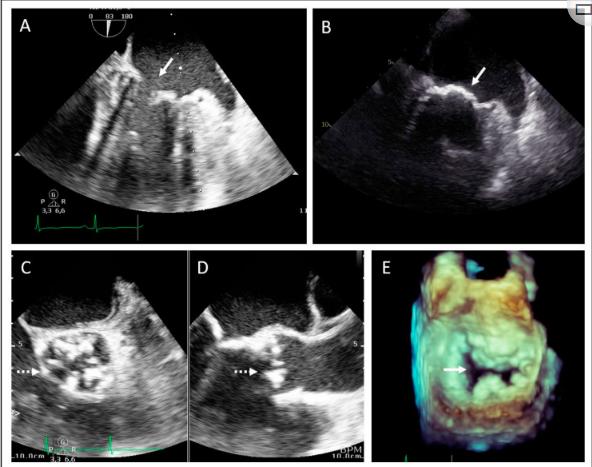

在第二个家族中,先证者是一名34岁的男性,在一次与工作相关的医疗筛查中发现心脏杂音后,被诊断为严重的主动脉瓣和二尖瓣狭窄以及临界左心室肥厚,心脏收缩功能保留。在诊断时,先证者仅表现出疲劳症状,但没有特定的心脏相关症状(即气短、外周水肿、胸痛或心悸)。图3显示经胸超声心动图图像,显示主动脉瓣(三尖瓣)(图3C,D)和二尖瓣环和小叶(图3A、B、E)。诊断后,患者接受了主动脉瓣和二尖瓣联合置换术。术后因三度房室传导阻滞植入了起搏器。患者因年轻时患有心脏瓣膜病和心室肥大以及心脏瓣膜病家族史而被转诊至临床遗传学家处。体检时,没有观察到系统性前体细胞受累的迹象。全面的身体和实验室评估也显示该患者没有脂肪营养不良或神经肌肉受累的迹象。

图3、家族2的先证者经食管超声心动图检查显示主动脉瓣狭窄和二尖瓣狭窄。(A,B)食道正中2室观显示严重的二尖瓣钙化(箭头)。(C)食管正中主动脉瓣短轴观和(D)长轴观,显示主动脉严重钙化(虚线箭头)。(E)舒张期二尖瓣三维数据显示明显钙化和狭窄(箭头)